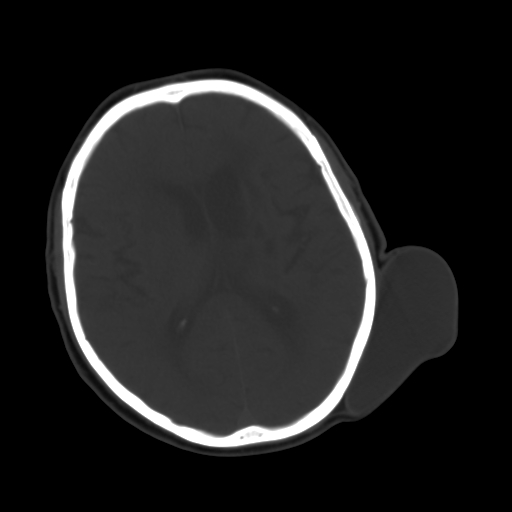

标题: CT25147:男,62岁,右侧肢体活动障碍不灵活三天。 [打印本页]

男,62岁,右侧肢体活动障碍不灵活三天,左侧头皮肿物十余年(ct值8hu)。

多发腔梗!皮下脂肪瘤!

1)多发性腔隙性脑梗塞。2)脑白质病。3)脑萎缩。4)左侧枕顶部头皮下皮样囊肿,不排除脂肪瘤。

1)多发性腔隙性脑梗塞。2)脑白质病。3)脑萎缩。4)左侧枕顶部头皮下皮样囊肿或表皮样囊肿。